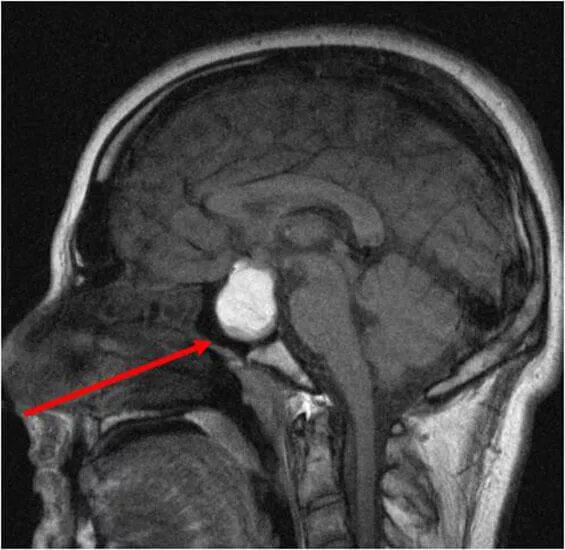

Опухоль гипофиза